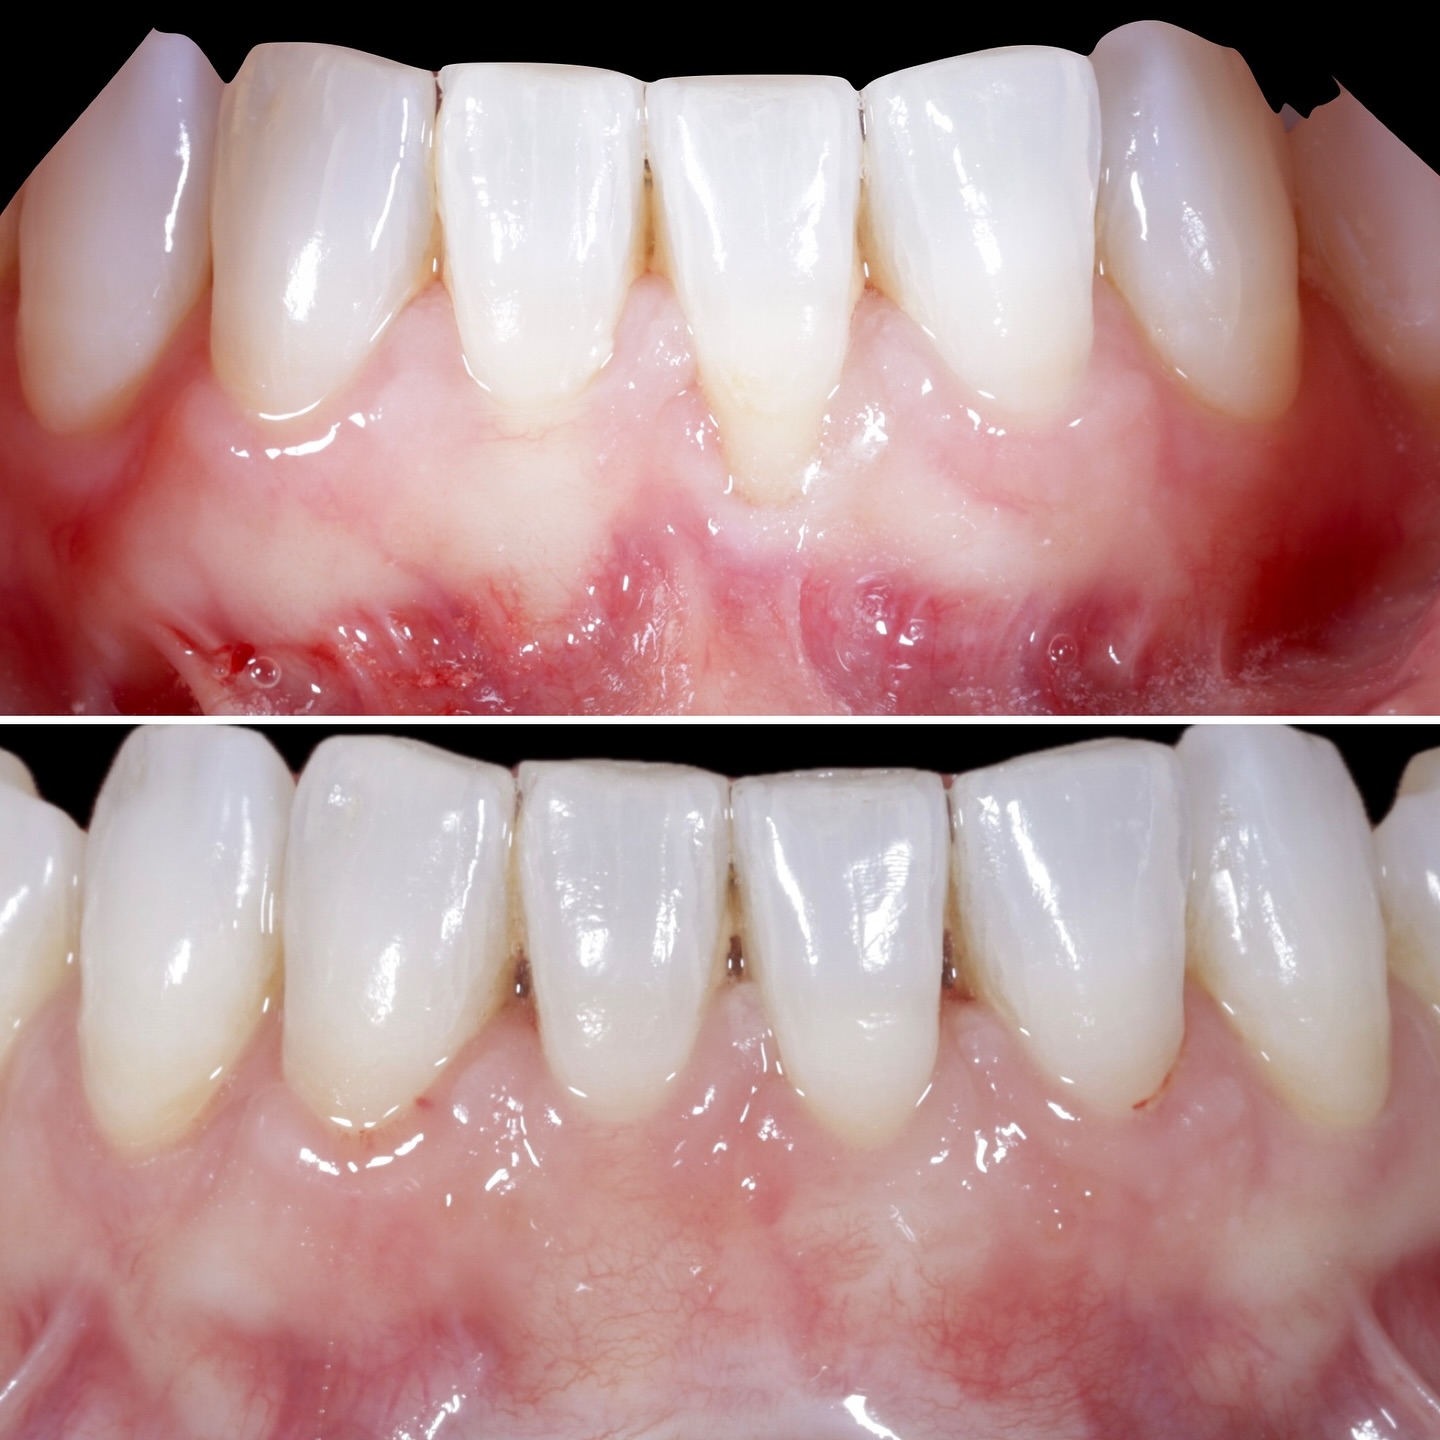

Durante una mañana, asistirás a una Cirugía Mucogingival de recubrimiento radicular de recesiones múltiples en IV y V sextante (36 a 43).

Gracias al uso del microscopio y a la proyección en tiempo real en pantalla, verás exactamente lo mismo que veo yo durante la cirugía, sin tener que estar

Podrás asistir a la planificación de casos y cirugía de injerto de tejido conectivo. Factores determinantes y elección de la técnica adecuada. Sumérgete en un protocolo predecible y técnicamente correcto para obtener resultados óptimos.

Se realizará todo el procedimiento con un microscopio operatorio, lo que permite al alumno ver toda la cirugía en directo en una pantalla en la sala de cirugía.

La formación comenzará con la presentación del caso clínico que se abordará durante el curso, seguida de una cirugía en directo, que permitirá observar paso a paso el procedimiento y la toma de decisiones clínicas. Durante la jornada se profundizará en los conceptos biológicos aplicados a

Durante una mañana, asistirás a una Cirugía Mucogingival de recubrimiento radicular de una recesión unitaria en 31 con frenillo asociado. Gracias al uso del microscopio y a la proyección en tiempo real en pantalla, verás exactamente lo mismo que veo yo durante la cirugía, sin tener que estar

Una estancia clínica pensada para quienes quieran iniciarse o dar un paso más en el campo de la cirugía mucogingival. Durante esta experiencia tendrás la oportunidad de aprender en directo cómo se planifica y se lleva a cabo una cirugía mucogingival mediante técnica de Túnel.